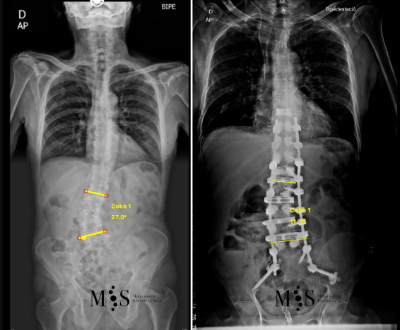

En aquests casos la cirurgia està indicada per corregir la deformitat i sobre tot per alleujar el dolor causat per l’escoliosi degenerativa. En els casos més severs d’escoliosi fins i tot pot ser necessari realitzar una osteotomía (tallar parcialment una vèrtebra) per poder redreçar la columna vertebral deformada del pacient.

Al Morgenstern Institute of Spine, utilitzem tècniques quirúrgiques endoscòpiques i percutànies per corregir les escoliosis degeneratives i permetre que el pacient es recuperi el més aviat possible. L’alta hospitalària es sol donar als pocs dies de la cirurgia.